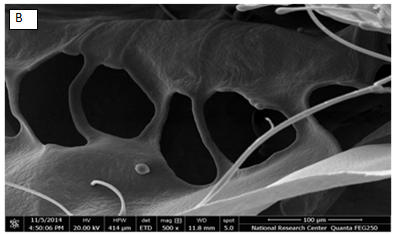

Fig. 3 (A-E) shows the morphology of the nasal inserts observed by (SEM). The process of freeze-drying is based on sublimation of the frozen water leading to the formation of pores or channels in the polymer that led to physically cross-linked hydrogel. All the samples were characterized by a sponge-like structure with presence of large voids that is an important parameter to ensure rapid hydration and gelation of the insert resulting in a larger surface/contact area and increased water uptake by capillary forces and to a reduced foreign body sensation when compared to other solid dosage forms, such as tablets [26]. Furthermore, fig. 4 shows the homogenous distribution of VRP on CS sponge like structure.

Fig. 4: Scanning electron micrograph of chitosan loaded VRP insert